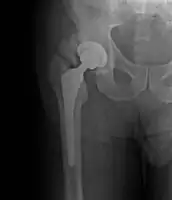

• Locations

• Hip most common - typically after ORIF (52% any grade, 19% Grade III-IV) or THA (43% any grade, 9% Grade III-IV)

Classification

Brooker Classification: (radiographic)

• I - islands of bone within the soft tissue (clinically silent)

• II - bone spurs from the pelvis or proximal femur; >= 1 cm gap between opposing surfaces (clinically insignificant)

• III - bone spurs from the pelvis or proximal femur; < 1 cm gap between opposing surfaces (clinically significant)

• IV - ankylosis (clinically significant)